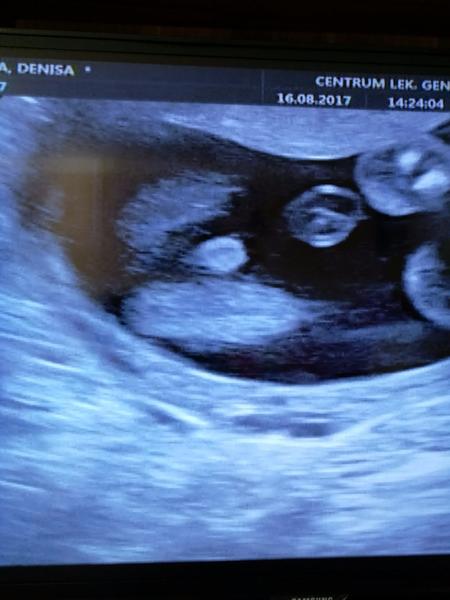

Ahoj maminky a budoucí maminky 😉 Prosím, poradila byste mi některá, co vidíte na fotce z ultrazvuku ve 20. týdnu za pohlaví? Určitě jste foteček viděly už mraky, proto vás žádám o radu...Nechci nikoho ovlivnit, proto svůj tip řeknu později 🙂 Děkuju moc!!!

Ahoj, bohužel jediné co vidím, je sladké malé miminko, ale pohlaví z této fotky určit nelze. Taky je dost brzy, ale já jsem kolem toho 14 tt pindíka zahlídla 🙂 Tohle zatím vypadá na holčičku, ale to je opravdu jen tím, že není nic jako pinďa přímo vidět!

@novamamina Tak prý opravdu holka🙂

Ja bych rekla, ze to je holcicka 🙂